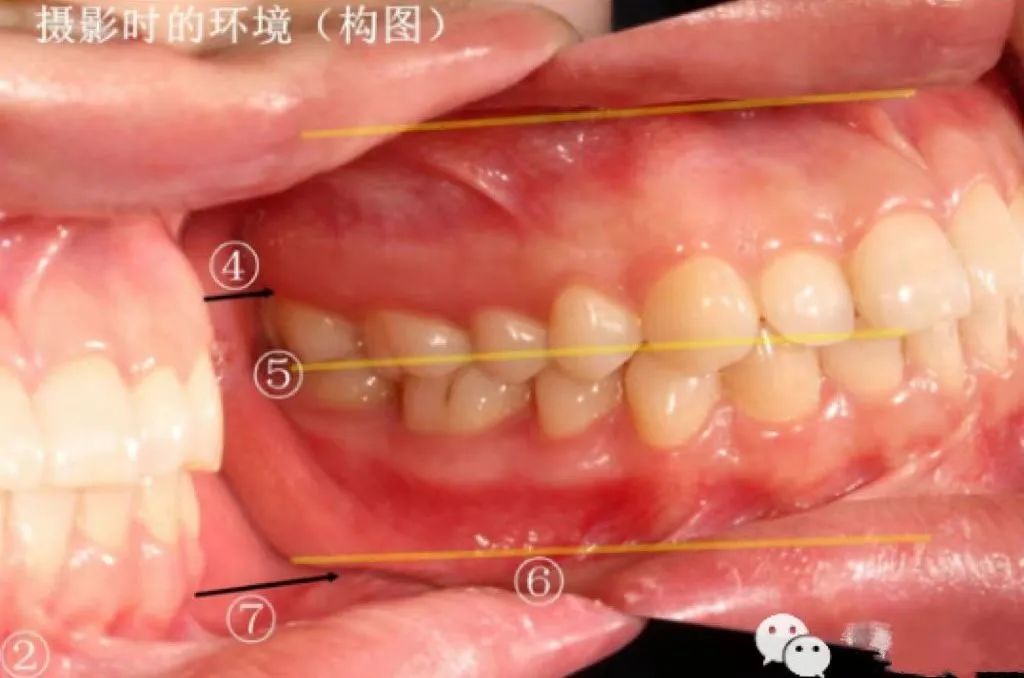

全牙列侧面咬合摄影

如何构图?